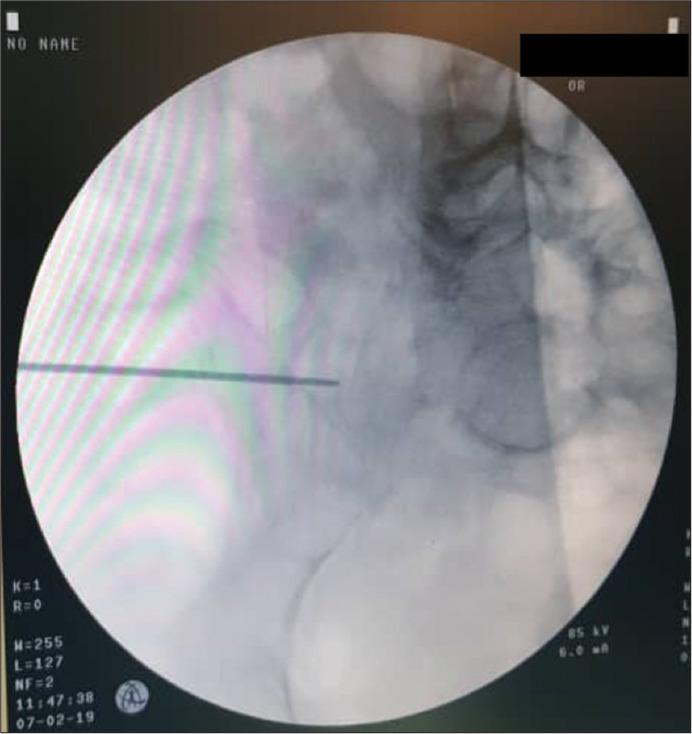

This retrospective study included 58 consecutive unstable posterior pelvic injury patients (36 sacral fractures and 22 sacroiliac joint disruptions) treated with percutaneous iliosacral screws between January 2015 and November 2019. Acceptable inlet radiographs show the anterior cortex of the S1 body superimposed on the S2 body. Acceptable outlet radiographs show the superior pubic symphysis at the level of the S2 foramen and visualize the S1 and S2 sacral foramina. In our technique, the screw was inserted at the inferior half of the outlet view and the posterior half of the inlet view. The time needed for screw insertion and the radiation exposure time was recorded. Intra and postoperative complications were documented. Postoperative computed tomography (CT) scans assessed screw position.

In total, 69 iliosacral screws were inserted in 58 patients. In postoperative CT scans, the screw position was assessed, 89.8% were in a secure position, and 10.2% had malposition. The mean operation time per screw was 21.18 min and the mean fluoroscopy time per screw was 112 s. There was no evidence of wound infection or iatrogenic neurovascular injury. No reoperation was performed.